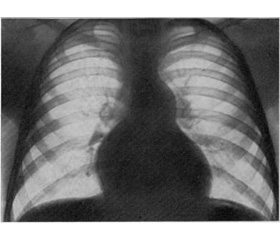

On the X-ray, cardiomegaly with a highly poor pulmonary circulation is found. The electrocardiogram shows dextrogram, signs of the right ventricle and right atrium hypertrophy. On the echocardiogram there is a stenosis on the valve level or of the subvalvular space, myocardium hypertrophy of the anterior wall of the right ventricle and of the interventricular septum, increase of the right atrium cavity, etc.